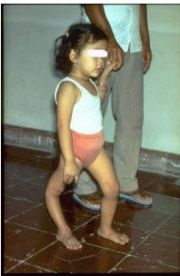

| 2021年7月26日 (一) 20:03 | 小儿麻痹症.jpg (文件) |  |

18 KB | Uploaded with SimpleBatchUpload | 3 |